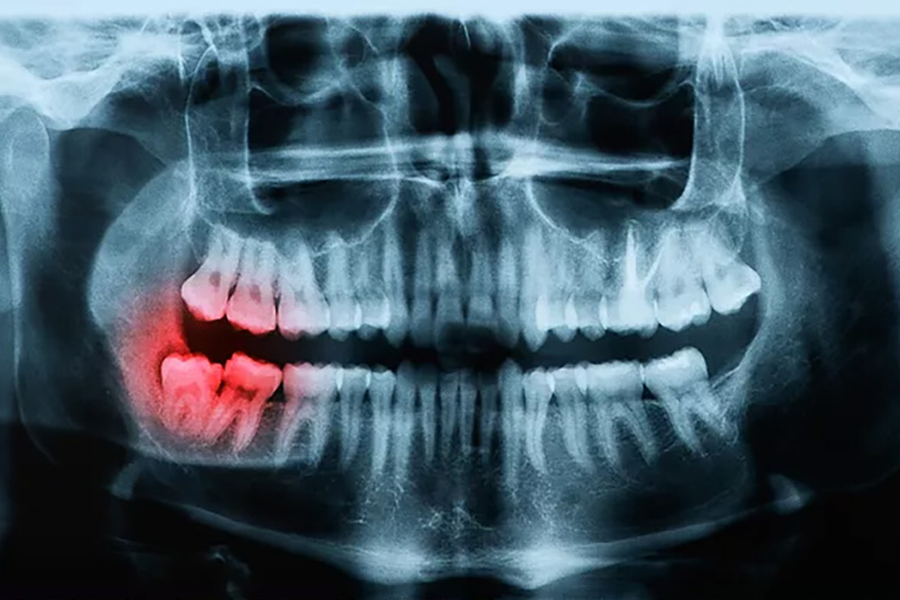

Tại sao phải chụp X-quang trước khi niềng răng?Niềng răng là một trong những phương pháp được nhiều người lựa chọn với mong muốn có một hàm răng chắc khỏe, đều đẹp. Nhưng không phải ai cũng biết lý do tại sao phải chụp Xquang trước khi niềng răng. Hãy tìm hiểu trong bài viết dưới đây.Chi tiết -